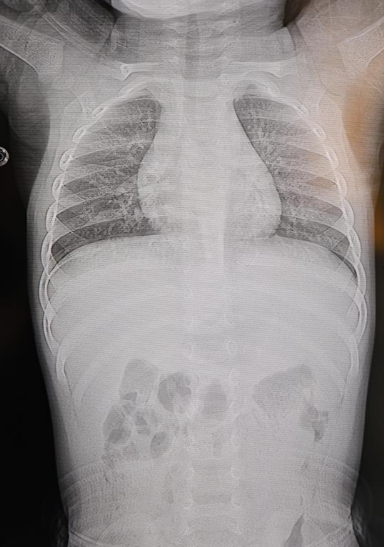

HG Hospital Beyin ve Sinir Cerrahisi Uzmanı Prof. Dr. İdris Altun tarafından yapılan tetkiklerde, yabancı cismin cilt altında, omurilik kanalına çok yakın bir noktada bulunduğu ve akciğer zarına doğru ilerlediği belirlendi. Bebek, genel anestezi uygulanmadan, lokal anestezi ve sedasyon eşliğinde ameliyata alındı. Yapılan başarılı müdahale ile yabancı cisim tamamen çıkarıldı.

Operasyon sırasında çıkarılan cismin, ince bir zımba teline benzer metal tel olduğu ve yaklaşık 2 santimetre uzunluğunda bulunduğu tespit edildi. Bebeğin sağlık durumunun iyi olduğu öğrenilirken, hasta aynı gün taburcu edildi.